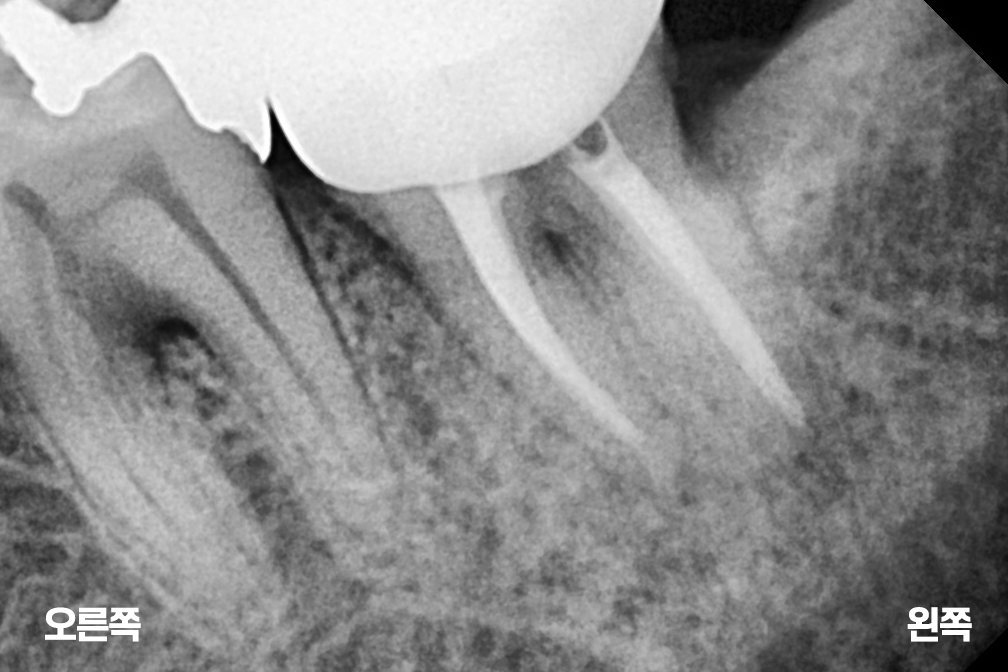

재신경치료

Before 2025년 8월 16일